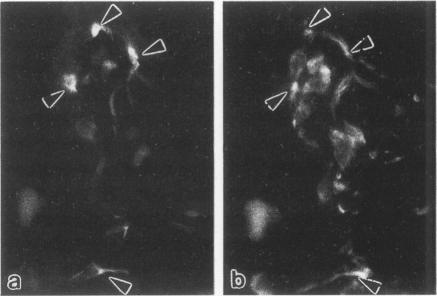

The authors studied by immunohistochemistry the intermediate filament (IF) protein profile of 66 frozen samples of breast tissue, including normal parenchyma, all variants of fibrocystic disease (FCD), fibroadenomas, cystosarcoma phylloides, and ductal and lobular carcinomas. Monoclonal antibodies (MAbs) to cytokeratins included MAb KA 1, which binds to polypeptide 5 in a complex with polypeptide 14 and recognizes preferentially myoepithelial cells; MAb KA4, which binds to polypeptides 14, 15, 16 and 19; individual MAbs to polypeptides 7, 13, and 16, 17, 18, and 19, and the MAb mixture AE1/AE3. The authors also applied three MAbs to vimentin (Vim), and three MAbs to glial filament protein (GFP). Selected samples were studied by double-label immunofluorescence microscopy and by staining sequential sections with some of the said MAbs, an MAb to alpha-smooth muscle actin, and well-characterized polyclonal antibodies for the possible coexpression of diverse types of cytoskeletal proteins. Gel electrophoresis and immunoblot analysis also were performed. All samples reacted for cytokeratins with MAbs AE1/AE3, although the reaction did not involve all cells. Monoclonal antibody KA4 stained preferentially the luminal-secretory cells in the normal breast and in FCD, whereas it stained the vast majority of cells in all carcinomas. Monoclonal antibody KA1 stained preferentially the basal-myoepithelial cells of the normal breast and FCD while staining tumor cell subpopulations in 4 of 31 carcinomas. Vimentin-positive cells were found in 8 of 12 normal breasts and in 12 of 20 FCD; in most cases, Vim-reactive cells appeared to be myoepithelial, but occasional luminal cells were also stained. Variable subpopulations of Vim-positive cells were noted in 9 of 20 ductal and in 1 of 7 lobular carcinomas. Glial filament protein-reactive cells were found in normal breast lobules and ducts and in 15 of 20 cases of FCD; with rare exceptions, GFP-reactivity was restricted to basally located, myoepithelial-appearing cells. Occasional GFP-reactive cells were found in 3 of 31 carcinomas. Evaluation of sequential sections and double-label immunofluorescence microscopy showed the coexpression of certain cytokeratins (possibly including polypeptides 14 and 17) with vimentin and alpha-smooth muscle actin together with GFP in some myoepithelial cells. The presence of GFP in myoepithelial cells was confirmed by gel electrophoresis and immunoblotting. Our results indicate that coexpression of cytokeratin with vimentin and/or GFP is comparatively frequent in normal basal-myoepithelial cells of the breast.(ABSTRACT TRUNCATED AT 400 WORDS)

作者采用免疫组织化学方法研究了66份乳腺组织冷冻样本的中间丝(IF)蛋白谱,这些样本包括正常实质组织、纤维囊性疾病(FCD)的所有变体、纤维腺瘤、叶状囊肉瘤以及导管癌和小叶癌。针对细胞角蛋白的单克隆抗体(MAb)包括与多肽5结合形成复合物并优先识别肌上皮细胞的MAb KA 1;与多肽14、15、16和19结合的MAb KA4;针对多肽7、13以及16、17、18和19的单个MAb,以及MAb混合物AE1/AE3。作者还应用了三种针对波形蛋白(Vim)的MAb和三种针对神经胶质丝蛋白(GFP)的MAb。通过双标记免疫荧光显微镜以及用上述部分MAb、一种针对α-平滑肌肌动蛋白的MAb和特性明确的多克隆抗体对连续切片进行染色,研究选定样本中不同类型细胞骨架蛋白的可能共表达情况。还进行了凝胶电泳和免疫印迹分析。所有样本与MAb AE1/AE3反应显示细胞角蛋白阳性,尽管并非所有细胞都有反应。单克隆抗体KA4优先染色正常乳腺和FCD中的腔分泌细胞,而在所有癌中它染色绝大多数细胞。单克隆抗体KA1优先染色正常乳腺和FCD的基底肌上皮细胞,而在31例癌中的4例中染色肿瘤细胞亚群。在12例正常乳腺中的8例以及20例FCD中的12例中发现波形蛋白阳性细胞;在大多数情况下,Vim反应性细胞似乎是肌上皮细胞,但偶尔也有腔细胞被染色。在20例导管癌中的9例以及7例小叶癌中的1例中注意到Vim阳性细胞的不同亚群。在正常乳腺小叶和导管以及20例FCD中的15例中发现神经胶质丝蛋白反应性细胞;除罕见例外,GFP反应性仅限于位于基底的、呈肌上皮样的细胞。在31例癌中的3例中偶尔发现GFP反应性细胞。对连续切片和双标记免疫荧光显微镜的评估显示,在一些肌上皮细胞中某些细胞角蛋白(可能包括多肽14和17)与波形蛋白、α-平滑肌肌动蛋白以及GFP共表达。通过凝胶电泳和免疫印迹证实了肌上皮细胞中存在GFP。我们的结果表明,在乳腺正常基底肌上皮细胞中细胞角蛋白与波形蛋白和/或GFP的共表达相对常见。(摘要截选至400字)